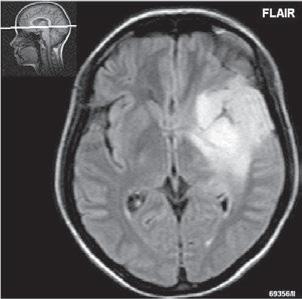

Roztroušená skleróza (RS) 189

Neuromyelitis optica (NMO) – Devicova nemoc 196

Akutní diseminovaná encefalomyelitida (ADEM) 199

Progresivní multifokální leukoencefalopatie (PML)